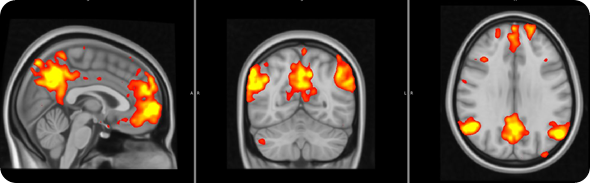

Fibro brain 3

How did fibromyalgia patients in your study respond to pain anticipation and relief and how did they compare to control participants?

FM patients exhibited reduced brain responses in response to visual cues for both pain anticipation as well as relief anticipation.

This reduced responsiveness was very widespread, and included the periaqueductal gray and the VTA.